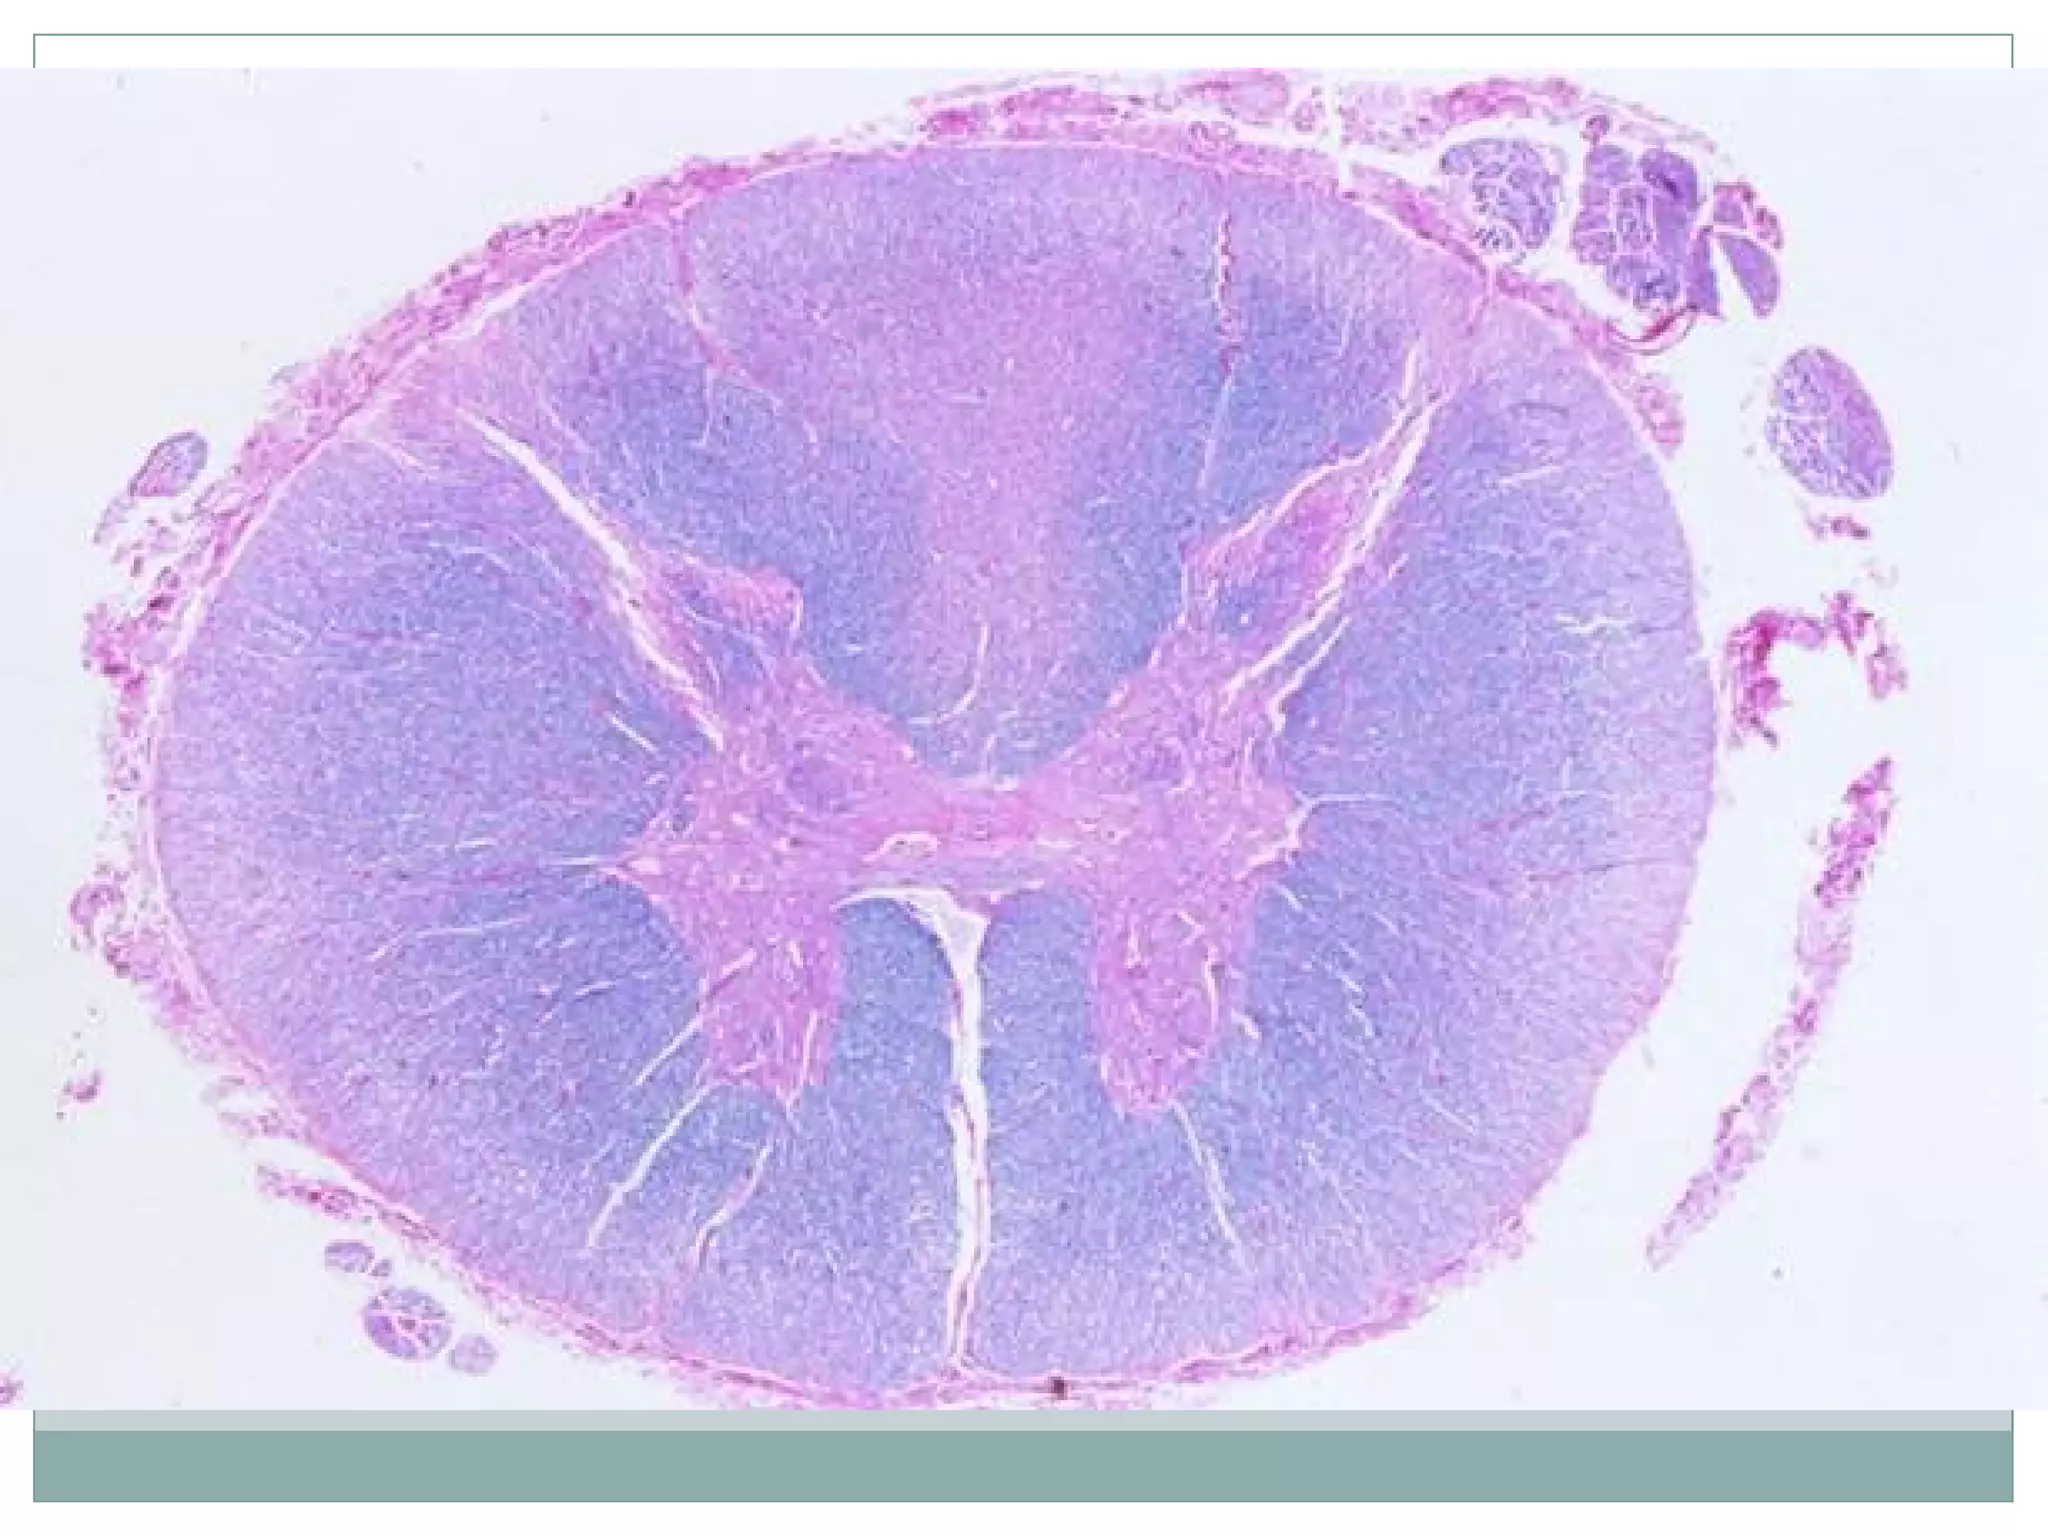

Нугасны арын болон хажуугийн

сэртэн бүтэц алдагдах,

миелэнгүйжих

Нугасны арын болонхажуугийн сэртэн бүтэц алдагдах, миелэнгүйжих